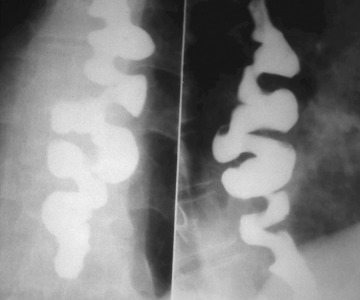

위조영술 검사는 바륨이라는 하얀 액체를 마시고 그 액체가 식도를 타고 내려가면서 위에 쌓였을 때 몸을 이리저리 뒤집어가면서 그 흑백화면을 보면서 읽어내는 검사방법입니다.

바륨현탁액, 요오드제제를 이용해 위의 이상 유무를 검사합니다. 이 용액은 X선 투과가 잘 안되는 물질로 이 용액을 마시고 X선이 발생되는 기계 위에서 몸을 이리저리 돌려가면서 검사를 받습니다. 기계가 알아서 돌아가는 것이 아니라 사람이 직접 그 기계 위해서 몸을 움직여 줘야 합니다.

X선이 발생하는 기계 위에 있으므로 그 방사선이 몸을 투과하므로 미량의 방사선 피폭이 있다는 것은 인지해야 합니다. 위조영술 검사방법은 위를 풍선처럼 팽창시켜 위벽에 조영제 코팅해 위벽 병변 유무를 검사하는 방법과 위가 팽창하지 않은 상태에서 위를 조영제로 채워 검사하는 두가지 방법이 있으며 일반적으로 두가지 다 시행해야 위벽과 안을 다 검사 할 수 있습니다.

하지만 위조영술 검사 장점도 분명히 존재합니다. 이는 그래도 위내시경 검사처럼 굵은 카메라를 삼켜야 하는 불편함이 없으며 노인이나 기저질환이 있는 환자도 위 검사를 받을 수 있고 식도에서 위 그리고 십이지장으로 이어지는 위장관의 전체적 모양과 연동운동을 관찰 할 수 있다는 점입니다.